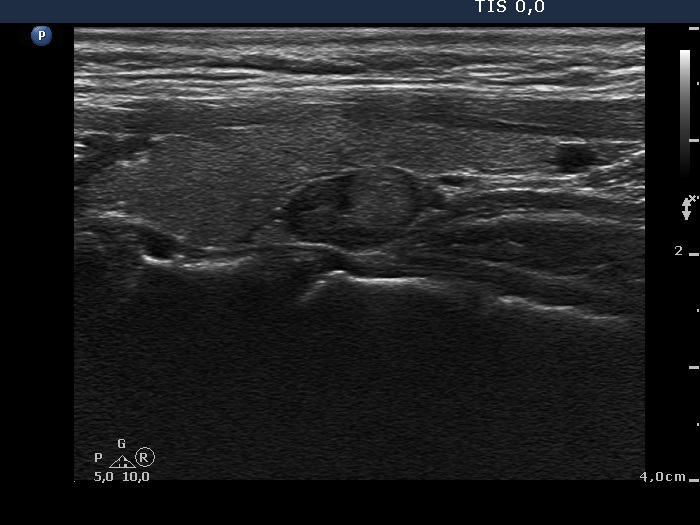

The borders of the nodule - case 2115 (ultrasonographic picture 11)

Left lobe, another longitudinal view.